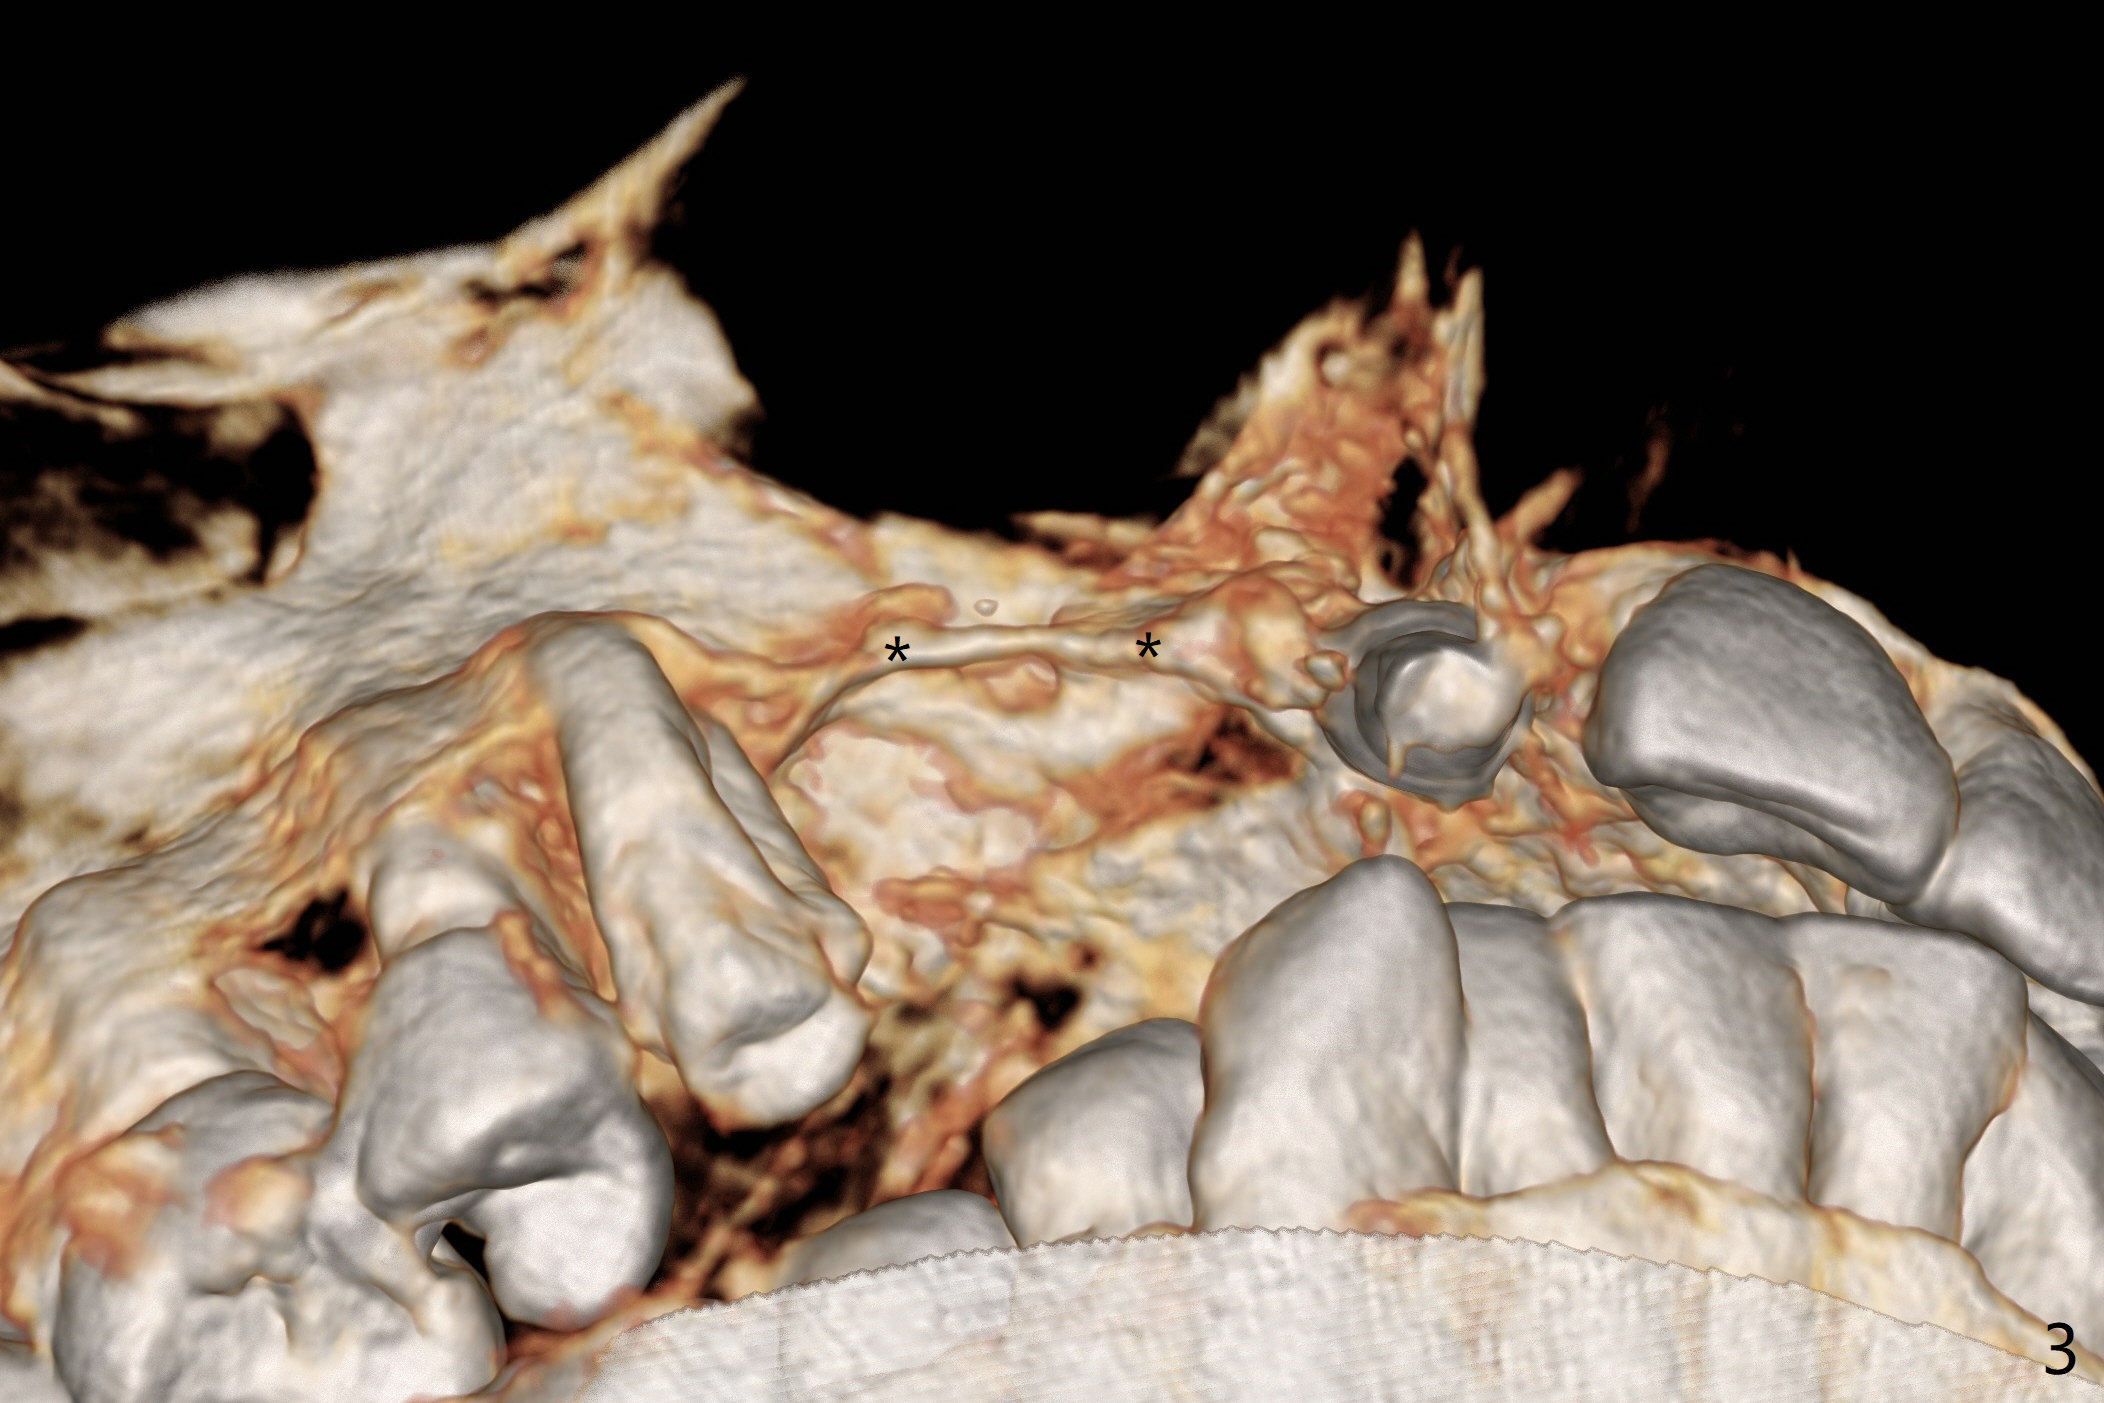

A 51-year-old woman lost the teeth #6 and 7 due to odontoma removal ~30 years ago. The area was restored with a FPD. The latter is removed with immediate implant at #8 8-9 months earlier. Particulate bone graft does not repair the bone deficiency at #6, 7 (Fig.2,3), although the soft tissue looks bulky (Fig.1). It appears that the palatal defect also needs a piece of bone block to fill in (Fig.4). The block will be harvested from the chin (Fig.5,6). If the block graft turns out to be impracticable, the periodontally compromised tooth #5 (bone loss, Fig.2,3,7) will be extracted for immediate implant. Initial osteotomy will be established in the palatal socket (Fig.8,9). Either a 2- (Fig.10) or 1- (Fig.11) piece implant will be placed. After wound healing, impression will be taken for a lab-fabricated provisional FPD.

An asymptomatic erythema develops at #8 10 months postop (Fig.12 *). A fistula forms 11 months postop (Fig.13 < ) and is associated with implant thread exposure (Fig. 14 >, as compared to Fig.2). It appears that bone graft and possible block graft are needed with PRF after debridement with Titanium brush.